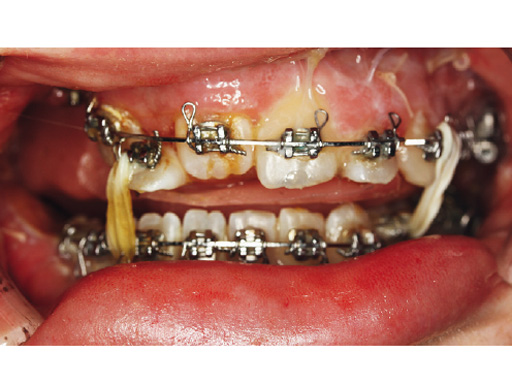

Case 2: Complex congenital deformity with distortion of alveolar processes and dentition, resulting in a 3.5 cm nonocclusion in the right maxillomandibular complex. Occlusion is exclusively controlled through the left second premolar to second molar. Piezosurgery was useful in this case due to complex anatomical deformities resulting in atypical positioning of the inferior alveolar canal on the right side. The cramped confines of dental and bony tissues in the deformed anatomy required an adequate type of osteotomy to do a significant yet controlled skeletal movement to overcome the vertical discrepancy intraorally, without changing the outer projection of the mandibular frame.

Case provided by Nils-Claudius Gellrich, Hannover, Germany